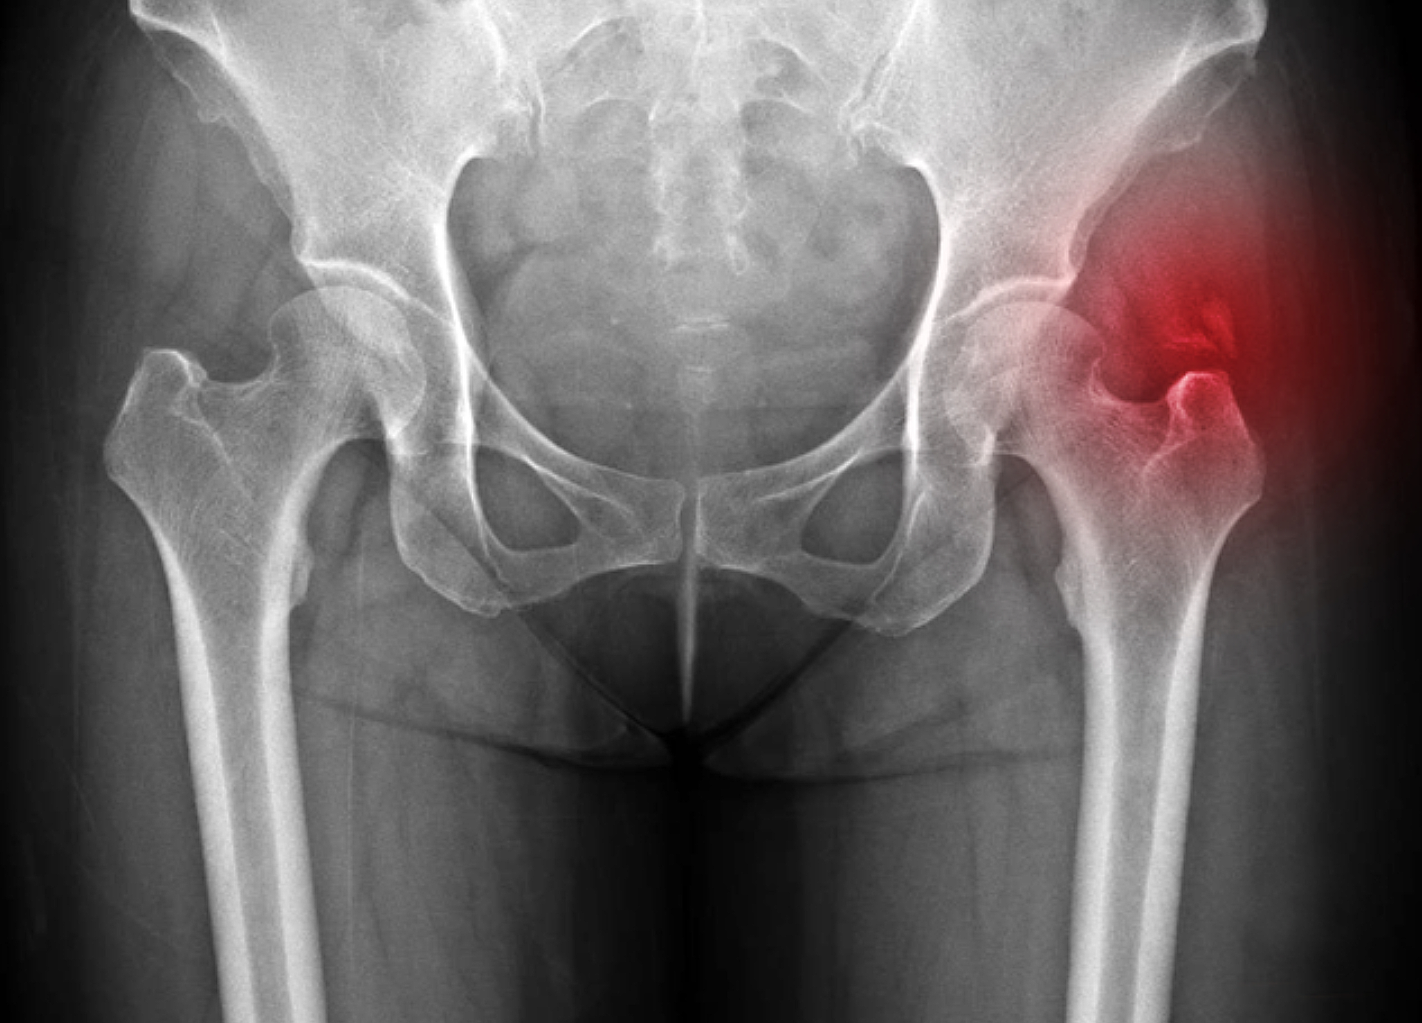

우리나라에서 발생하는 고관절 통증 증상의 가장 큰비중(70%)을 차지하는 대퇴골두 무혈성 괴사는특히 30~50대 젊은 남성에서 많이 발생하는 것으로 알려져 있습니다. 이 질환은 고관절의 기능을 완전히 잃게 할수 있어 주의가 필요합니다.

고관절은 골반 뼈 속에 공처럼 생긴 대퇴골의 골두가 맞물린 관절입니다. 대퇴골두는 다른 부위에 비해 혈액 순환 장애가 쉽게 올 수 있으며, 혈액 순환 장애는 대퇴골두 무혈성 괴사를 유발합니다. 뼈가 썩으면 몸의 하중을 정상적으로 견디지 못해 미세구조에 골절이 생기고, 심각한 통증이 발생합니다.

고관절 통증 증상은 조기에 발견하고 치료받는 것이 무엇보다 중요합니다. 고관절 손상이 심하지 않고 통증이 가볍다면 약물치료와 운동치료 등 보존적 치료를 통해 회복할 수 있습니다. 하지만 고관절 손상이 심하고 일상생활에 지장을 줄 만큼의 심한 고관절 통증 증상이 있는 경우라면 괴사된 관절을 제거하고 인공관절을 삽입하는 고관절의 인공관절 치환술을 해야 합니다.